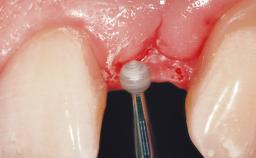

Immediate Flapless Placement of an Implant in a Maxillary Right Lateral Incisor Site

This 43-year-old male patient, a non-smoker, came to our practice because of a fracture of tooth 12 caused by a bicycle accident. Due to the combined para- and infrabony crown and root fracture, tooth extraction, and subsequent implant placement were suggested to the patient as the therapy of choice. The patient had high esthetic expectations with regard to the treatment outcome and asked for an immediate fixed provisional restoration. His individual esthetic risk profile summed up to a medium esthetic risk.

Soft Tissue Contour and Volume Ideal